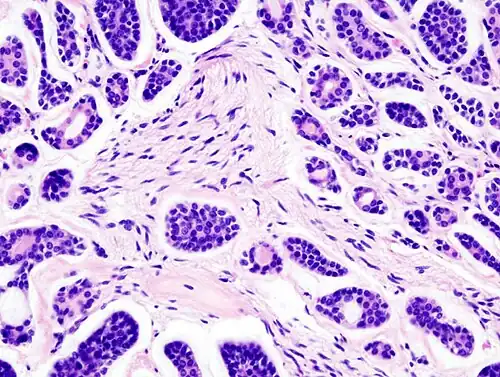

Micrograph of an adenoid cystic carcinoma of a salivary gland (right of image): Normal serous glands, typical of the parotid gland, are also seen (left of image), H&E stain.

Adenoid cystic carcinoma is a rare type of cancer that can exist in many different body sites. This tumor most often occurs in the salivary glands, but it can also be found in many anatomic sites, including the breast,[1][2] lacrimal gland, lung, brain, Bartholin gland, trachea, and the paranasal sinuses.